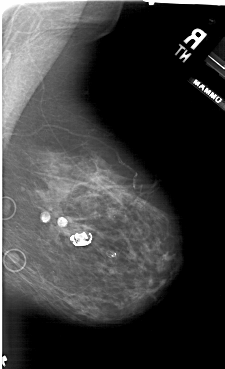

A_1941_1.LEFT_CC

LEFT_CC LINES 5701 PIXELS_PER_LINE 3976 BITS_PER_PIXEL 12 RESOLUTION 43.5 OVERLAY

FILE: A_1941_1.LEFT_CC.OVERLAY

TOTAL_ABNORMALITIES 1

ABNORMALITY 1

LESION_TYPE CALCIFICATION TYPE PLEOMORPHIC DISTRIBUTION CLUSTERED

ASSESSMENT 4

SUBTLETY 2

PATHOLOGY BENIGN

TOTAL_OUTLINES 1

BOUNDARY